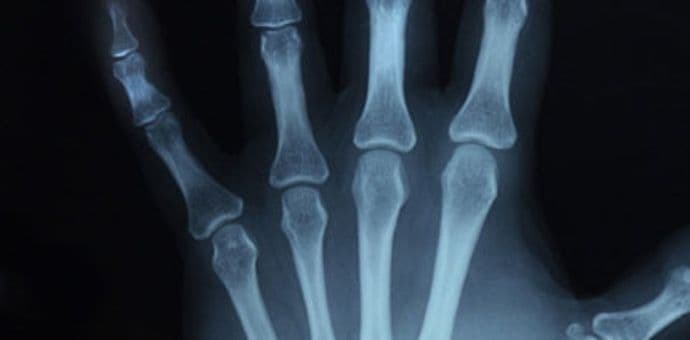

Rentgena: snimci imaju ograničenu vrijednost u postavljanju dijagnoze i praćenju bolesti. Ova metoda je značajna za procjenu postojanja i težine deformiteta i preloma.